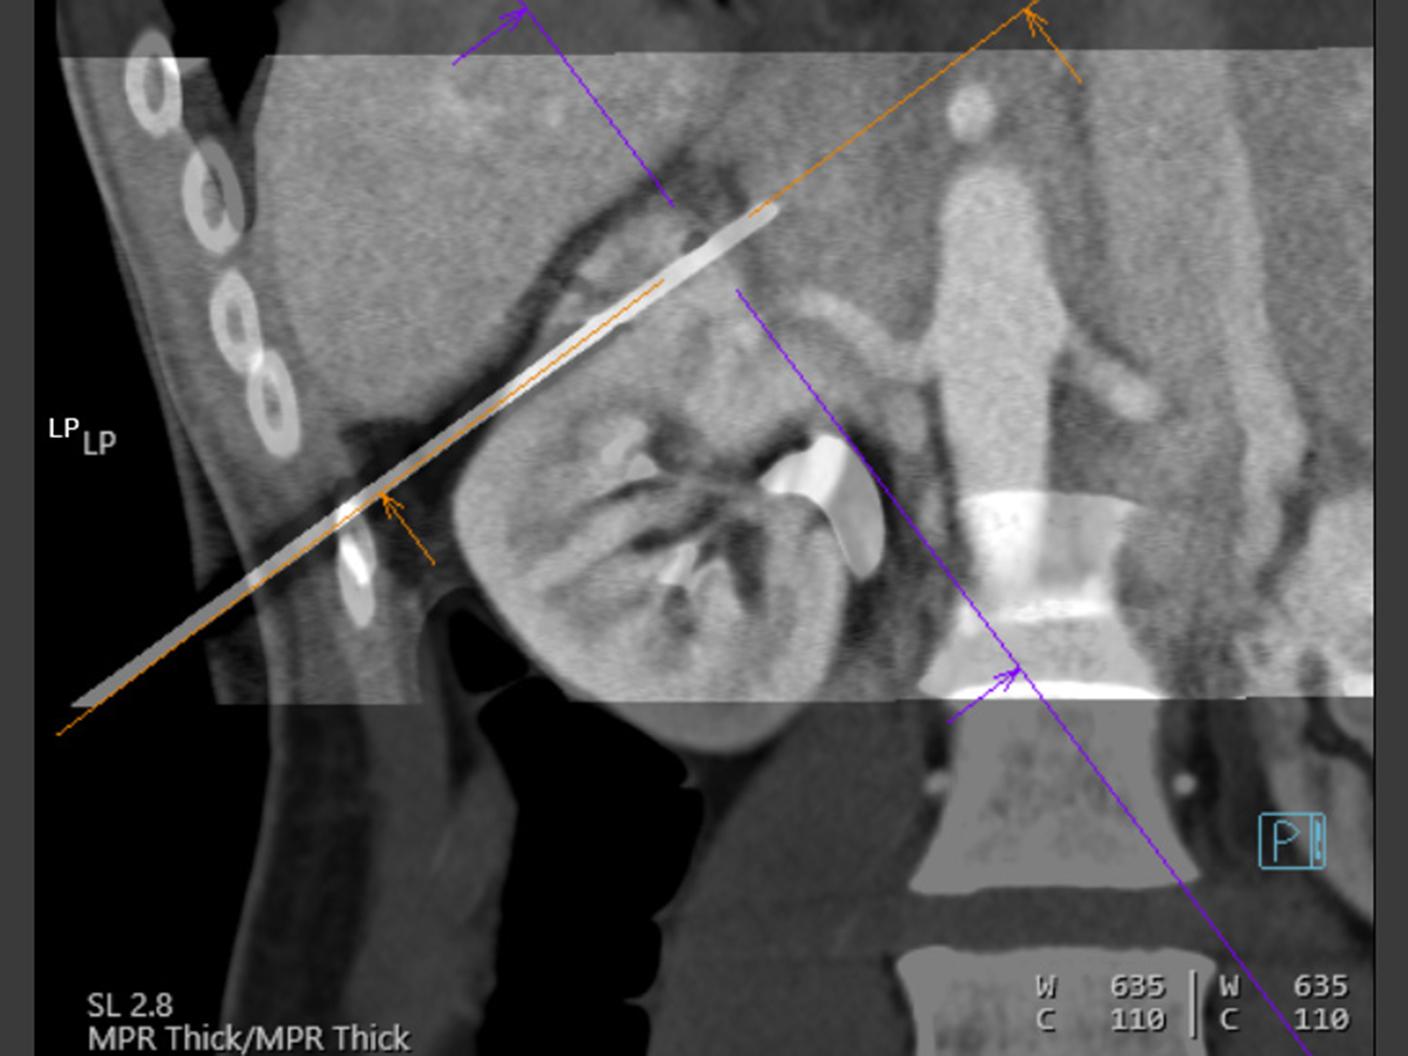

At the heart of NAEOTOM Alpha® is a radically new photon-counting detector. The QuantaMax detector directly converts X-rays into an electrical signal, which is then used to create an image. The energy of each X-ray is measured, so spectral information is available for every scan, and the images are contrast-rich with high spatial resolution at the same dose. Combining the high spatial resolution of the QuantaMax photon-counting detector with our Dual Source temporal resolution enables the visualization of fine details for increased diagnostic confidence.

QuantaMax, the first photon-counting detector, overcomes the limitations of conventional CT detectors by providing data at high spatial resolution, without electronic noise and with improved contrast-to-noise ratio.

Vectron X-ray tube enables high image quality, even for patients with high BMI. The microfocal spot (0.4 mm x 0.5 mm) allows to utilize the high spatial resolution of the QuantaMax detectors.

0.11 mm (in-plane) in Quantum HD